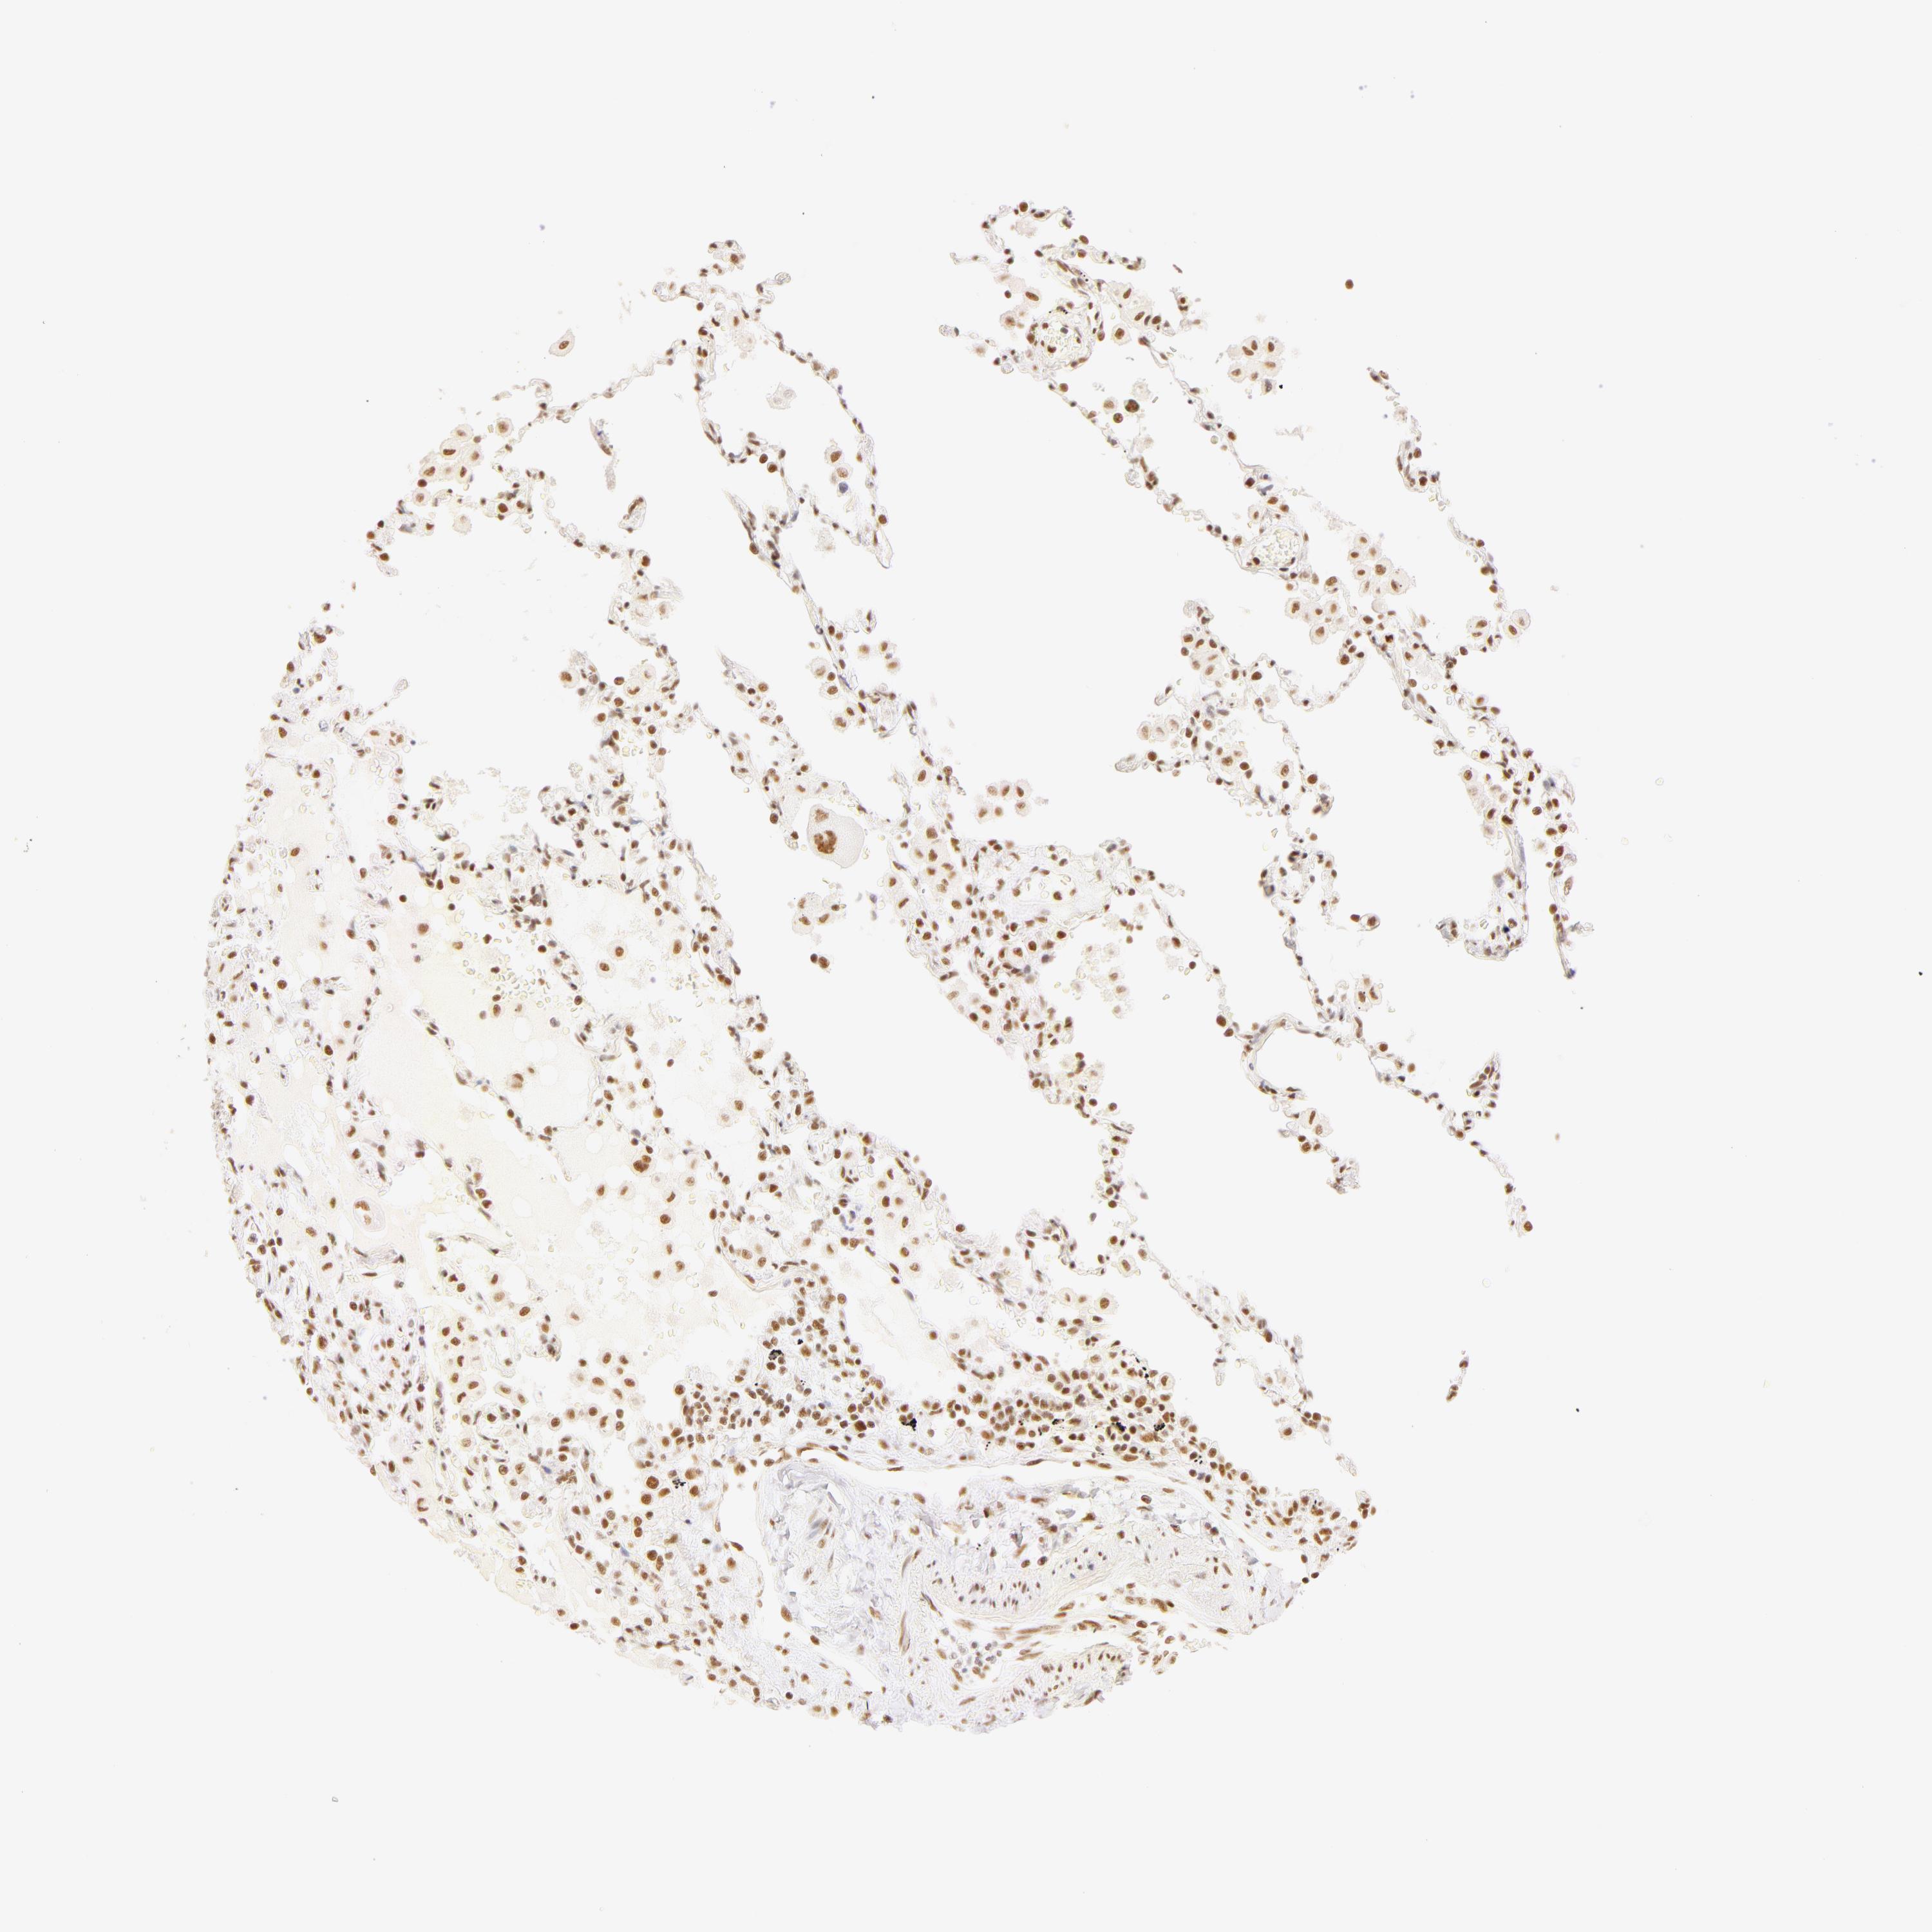

LUNG SQUAMOUS CELL CARCINOMA (TCGA) - Interactive survival scatter ploti

The Survival Scatter plot shows the clinical status (i.e. dead or alive) for all individuals in the patient cohort, based on the same data that underlies the corresponding Kaplan-Meier plots. Patients that are alive at last time for follow-up are shown in blue and patients who have died during the study are shown in red.

The x-axis shows the expression levels (FPKM) of the investigated gene in the tumor tissue at the time of diagnosis. The y-axis shows the follow-up time after diagnosis (years). Both axes are complimented with kernel density curves demonstrating the data density over the axes. The top density plot shows the expression levels (FPKM) distribution among dead (red) and alive patients (blue). The right density plot shows the data density of the survived years of dead patients with high and low expression levels respectively, stratified using the cutoff indicated by the vertical dashed line through the Survival Scatter plot. This cutoff is automatically defined based on the FPKM cutoff that minimizes the p-score. The cutoff can be changed by dragging the vertical line or by entering a cutoff value in the square labeled "Current cut-off".

Under the Survival Scatter plot the p-score landscape (black curve; left axis) is shown together with dead median separation (red curve; right axis). Dead median separation is the difference in median mRNA expression between patients who have died with high and low expression, respectively. It is calculated as follows: median FPKM expression of dead patients with high expression - median FPKM expression of dead patients with low expression. This is intended to aid the user in visually exploring custom cutoffs and the associated p-scores and dead median separation.

Individual patient data is displayed and can be filtered by clicking on one or more of the category buttons on the top of the page. Categories describing expression level and patient information include: high, low, alive, dead, female, male and tumor stages. The scale of the x-axis can be toggled between linear and log-scale by clicking on the "x log" button. Mouse-over function shows TCGA ID, patient information and mRNA expression (FPKM) for each patient.

& Survival analysisi

Kaplan-Meier plots summarize results from analysis of correlation between mRNA expression level and patient survival. Patients were divided based on level of expression into one of the two groups "low" (under cut off) or "high" (over cut off). X-axis shows time for survival (years) and y-axis shows the probability of survival, where 1.0 corresponds to 100 percent.

RBM39 is not prognostic in Lung Squamous Cell Carcinoma (TCGA)

: 29.89

P scorei

N/A

Average pTPM 25.4

Number of samples 489